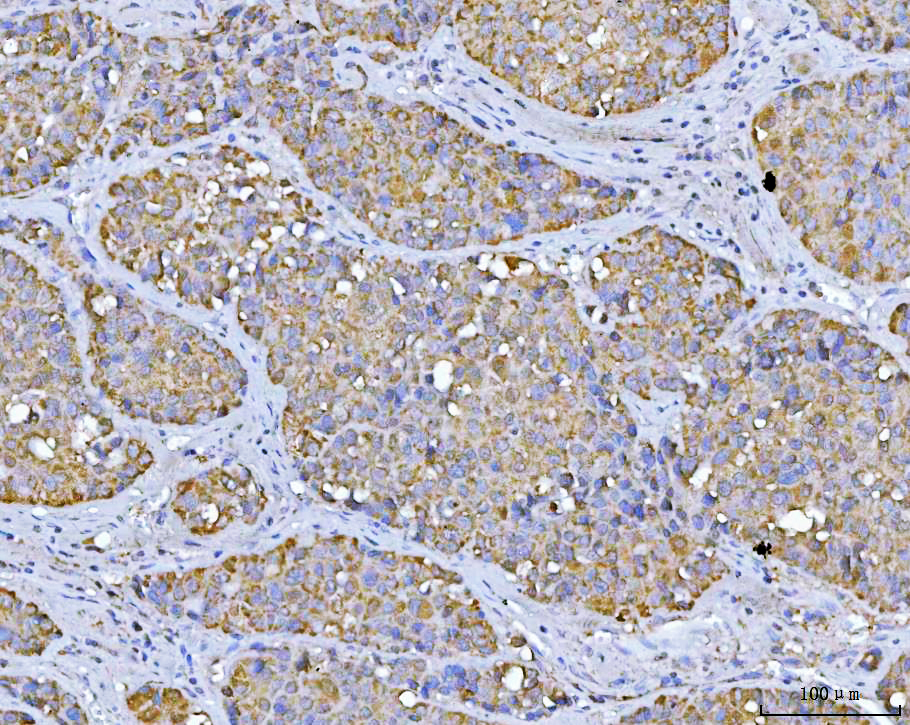

IHC analysis of VDAC1 using anti-VDAC1 antibody (BA3754).

VDAC1 was detected in a paraffin-embedded section of human ovarian cancer tissue. The tissue section was developed using HRP Conjugated Rabbit IgG Super Vision Assay Kit (Catalog # SV0002) with DAB (Catalog # AR1027) as the chromogen.